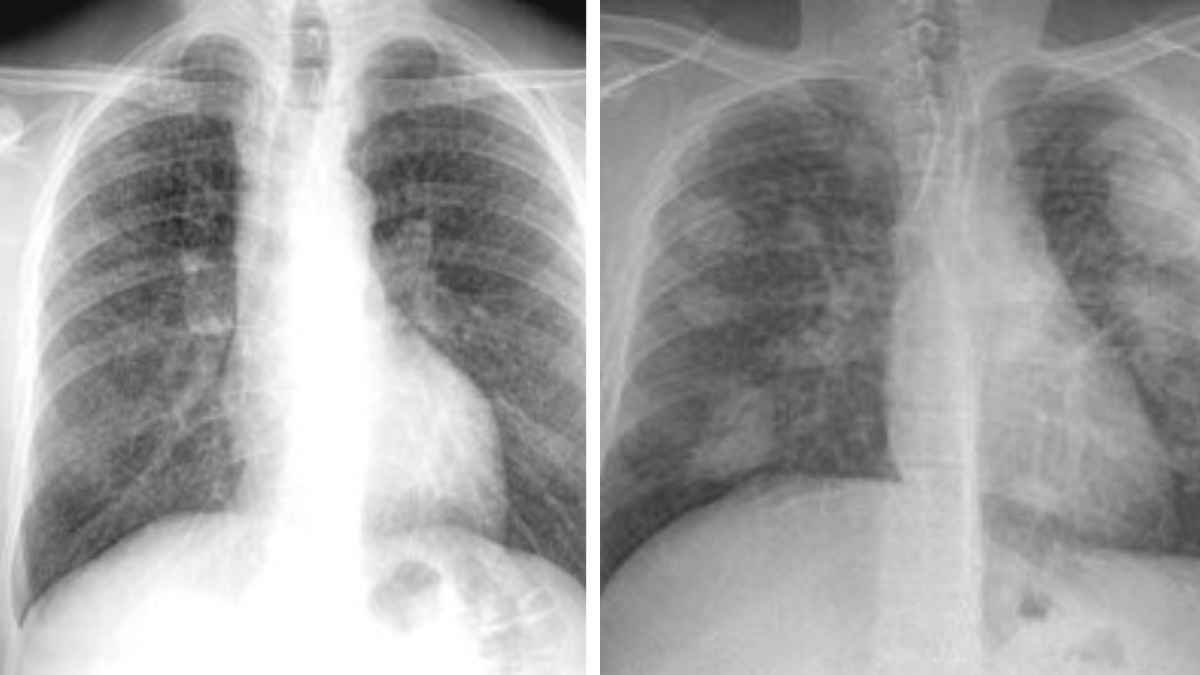

Los trabajadores expuestos a niveles peligrosos de polvo, como los de la minería y la extracción de piedra, son los principales beneficiarios de esta reforma. La silicosis, una enfermedad pulmonar grave que se desarrolla por la inhalación prolongada de polvo de sílice, afecta principalmente a trabajadores de sectores como la minería exterior, la extracción de granito y pizarra, así como aquellos que trabajan en empresas de transformación de mineral.